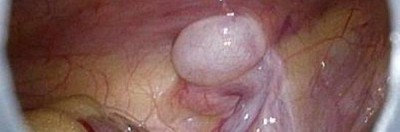

Hämatochezie bei drei Tage altem Neugeborenen

Ein neugeborener Junge und seine Mutter werden nach der Geburt zur Überwachung stationär aufgenommen, weil aufgrund einer maternalen Grunderkrankung eine transiente neonatale Myasthenia gravis auftreten kann. Zunächst verläuft alles unauffällig, bis der Junge an seinem dritten Lebenstag Blut im Stuhl hat. Welchen Grund vermuten Sie?